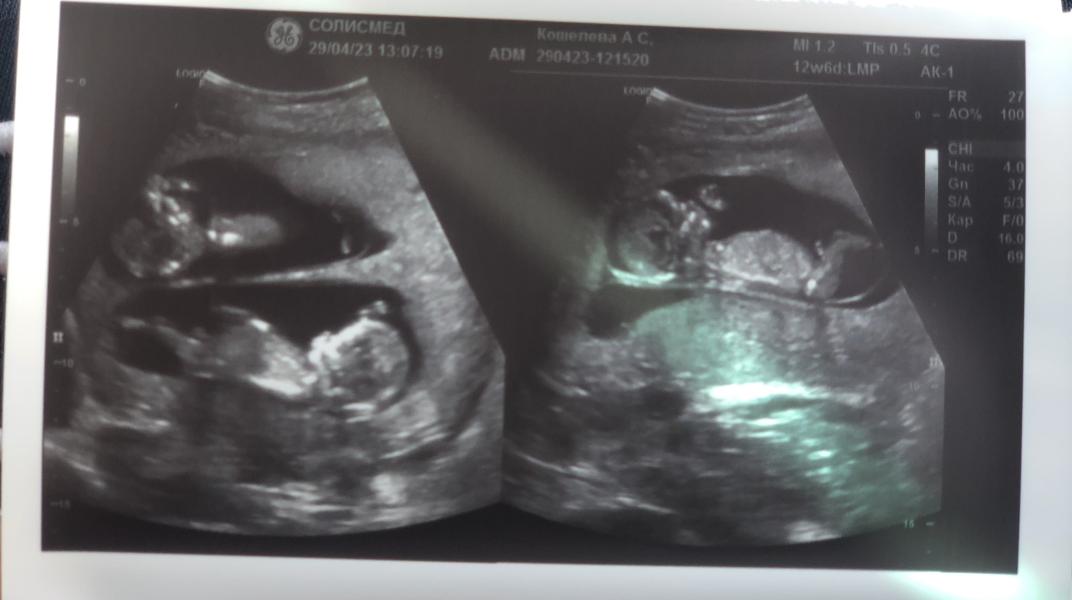

Ну что 14 недель , мы ждем двух мальчишек 💙💙

Мальчишки 😍 какая прелесть , сегодня прям листаю мои мечты 💭